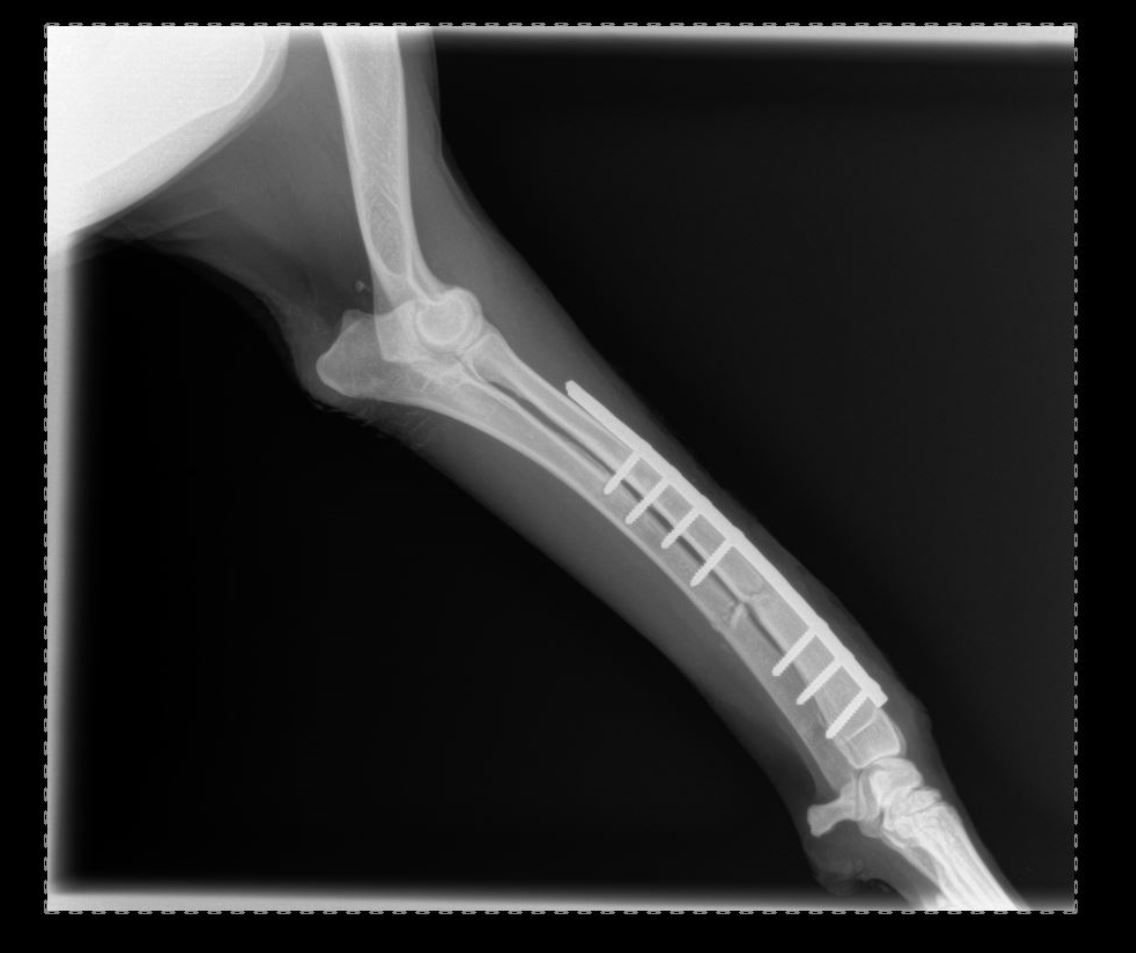

Chirurgies orthopediques:

-réduction des fractures (pose divers implants plaques broches etc),

Pose implant plaque DCP